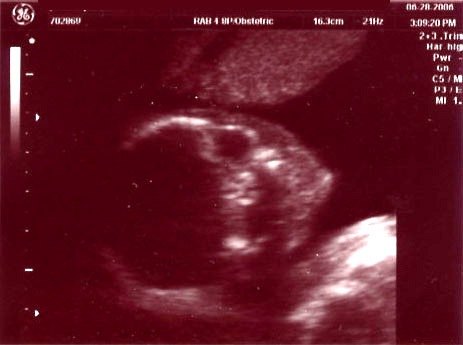

| June 28, 2006 - Twenty Week Ultrasound: IT'S A BOY!!! |

Today was probably the

longest day of my life having to wait for our 3:00pm appointment. I

went to work today, but didn't get much done since I was so excited to

finally find out what we were having. We got to the doctor's and they

took us right away. Within 44 seconds of the technician turning on the

ultrasound machine, she showed us the picture of the legs spread wide open

and it was obvious that we were having a boy!! He was so active

throughout the entire ultrasound, kicking and turning all over the place.

He is absolutely beautiful!!! I am in love with him already. He

weighed 13.5 ounces and he is perfect and healthy!! We are so excited

to start planning the nursery for our little man. Here are the

ultrasound pics from today. Enjoy!! ~Jen

Head shot of the little man |